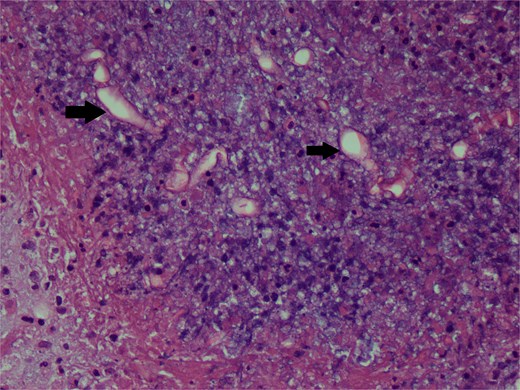

The whole arm was edematous, with evident flexion contracture at the elbow joint. The median nerve was intact. Ulnar and radial could not be assessed due to excessive edema. Her histopathology reports showed chronic granulomatous inflammation and invasive fungal infection, likely mucormycosis, and were negative for malignancy (Figs 2 and 3).

Periodic Acid Schiff stain photomicrograph showing broad-based aseptate fungal hyphae and spores (arrows).